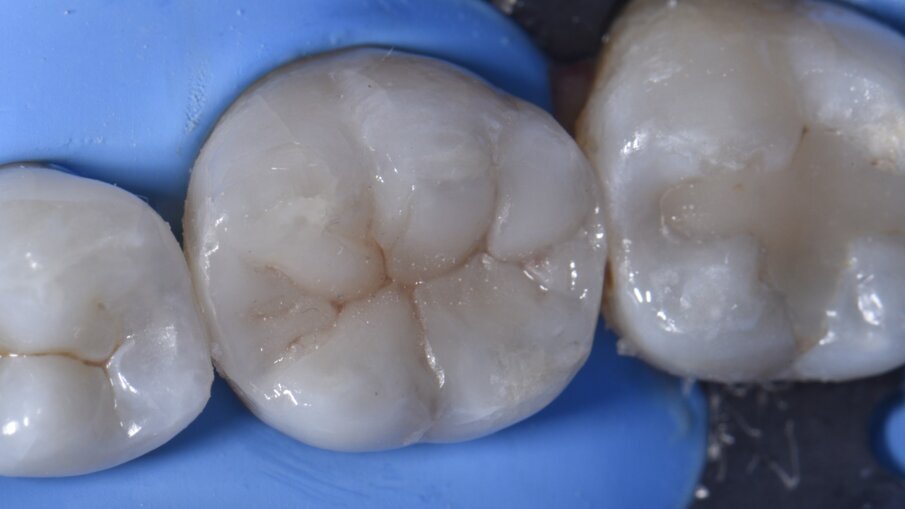

Come primo passo, si è scelto di ricostruire la parete mesiale (Fig. 3). Microstrati di un A2 fluido (Majesty esthetic, Kuraray Noritake) sono stati posizionati dopo un approccio di tipo total etch con MPa Bond (Clinicians Choice). A questo è stato permesso di disaccoppiarsi con il tempo per consentire la maturazione e l’ibridazione finale del legame alla dentina per il massimo rafforzamento del legame microtensile. La parete prossimale è stata ricostruita in strati orizzontali con incrementi di 1 mm in modo occlusale come prescritto dalla tecnica di Nikolaenko et al., consentendo valori massimi di forza di adesione microtensile. Dopo la polimerizzazione per una durata di 20 secondi, il gruppo della matrice sezionale è stato rimosso, l’anatomia del punto di contatto e la forza valutate con il filo interdentale prima dell’assemblaggio della matrice per ricostruire la parete prossimale in modo simile (Fig. 4). A seguito della costruzione della parete distale e dei relativi controlli, si è creata una situazione di Classe 1, priva di anelli di tensione e altri accessori che possono impedire l’accesso per la stratificazione occlusale (Fig. 5). La preferenza dell’autore di ricostruire una parete alla volta con matrici mesiali e distali posizionate separatamente attraverso il processo è in contrasto con i risultati della forza di contatto prossimale (PCS) di Sabre et al., che promuovono il posizionamento simultaneo di assemblaggi mesiali e distali. L’autore ritiene che il primo metodo sia più prevedibile soprattutto su denti più piccoli come i premolari, dove possono esserci difficoltà fisiche con il posizionamento simultaneo di matrici mesiali e distali a causa della necessità di sovrapporre Slick Bands insieme al rischio di comportamento a fisarmonica della matrice.

Il piano occlusale è stato anche microstratificato orizzontalmente con un composito fluido bianco opaco (tonalità Herculite Ultra Flowable XL2, KavoKerr) per bloccare la dentina scura (Fig. 5) prima del completamento della stratificazione si è usata una tonalità A2 di Voco Grandio SO. Le tinte occlusali sono state applicate utilizzando il marrone (Final Touch, Voco) (Fig. 6). Nel complesso, una sessione di restauro molto soddisfacente seguendo un protocollo graduale che riduce lo stress, aumenta la prevedibilità e consente prestazioni ottimali dei materiali e della ricostruzione estetica della struttura del dente mancante in una procedura piacevole sia per il paziente che per il medico (Fig. 7).